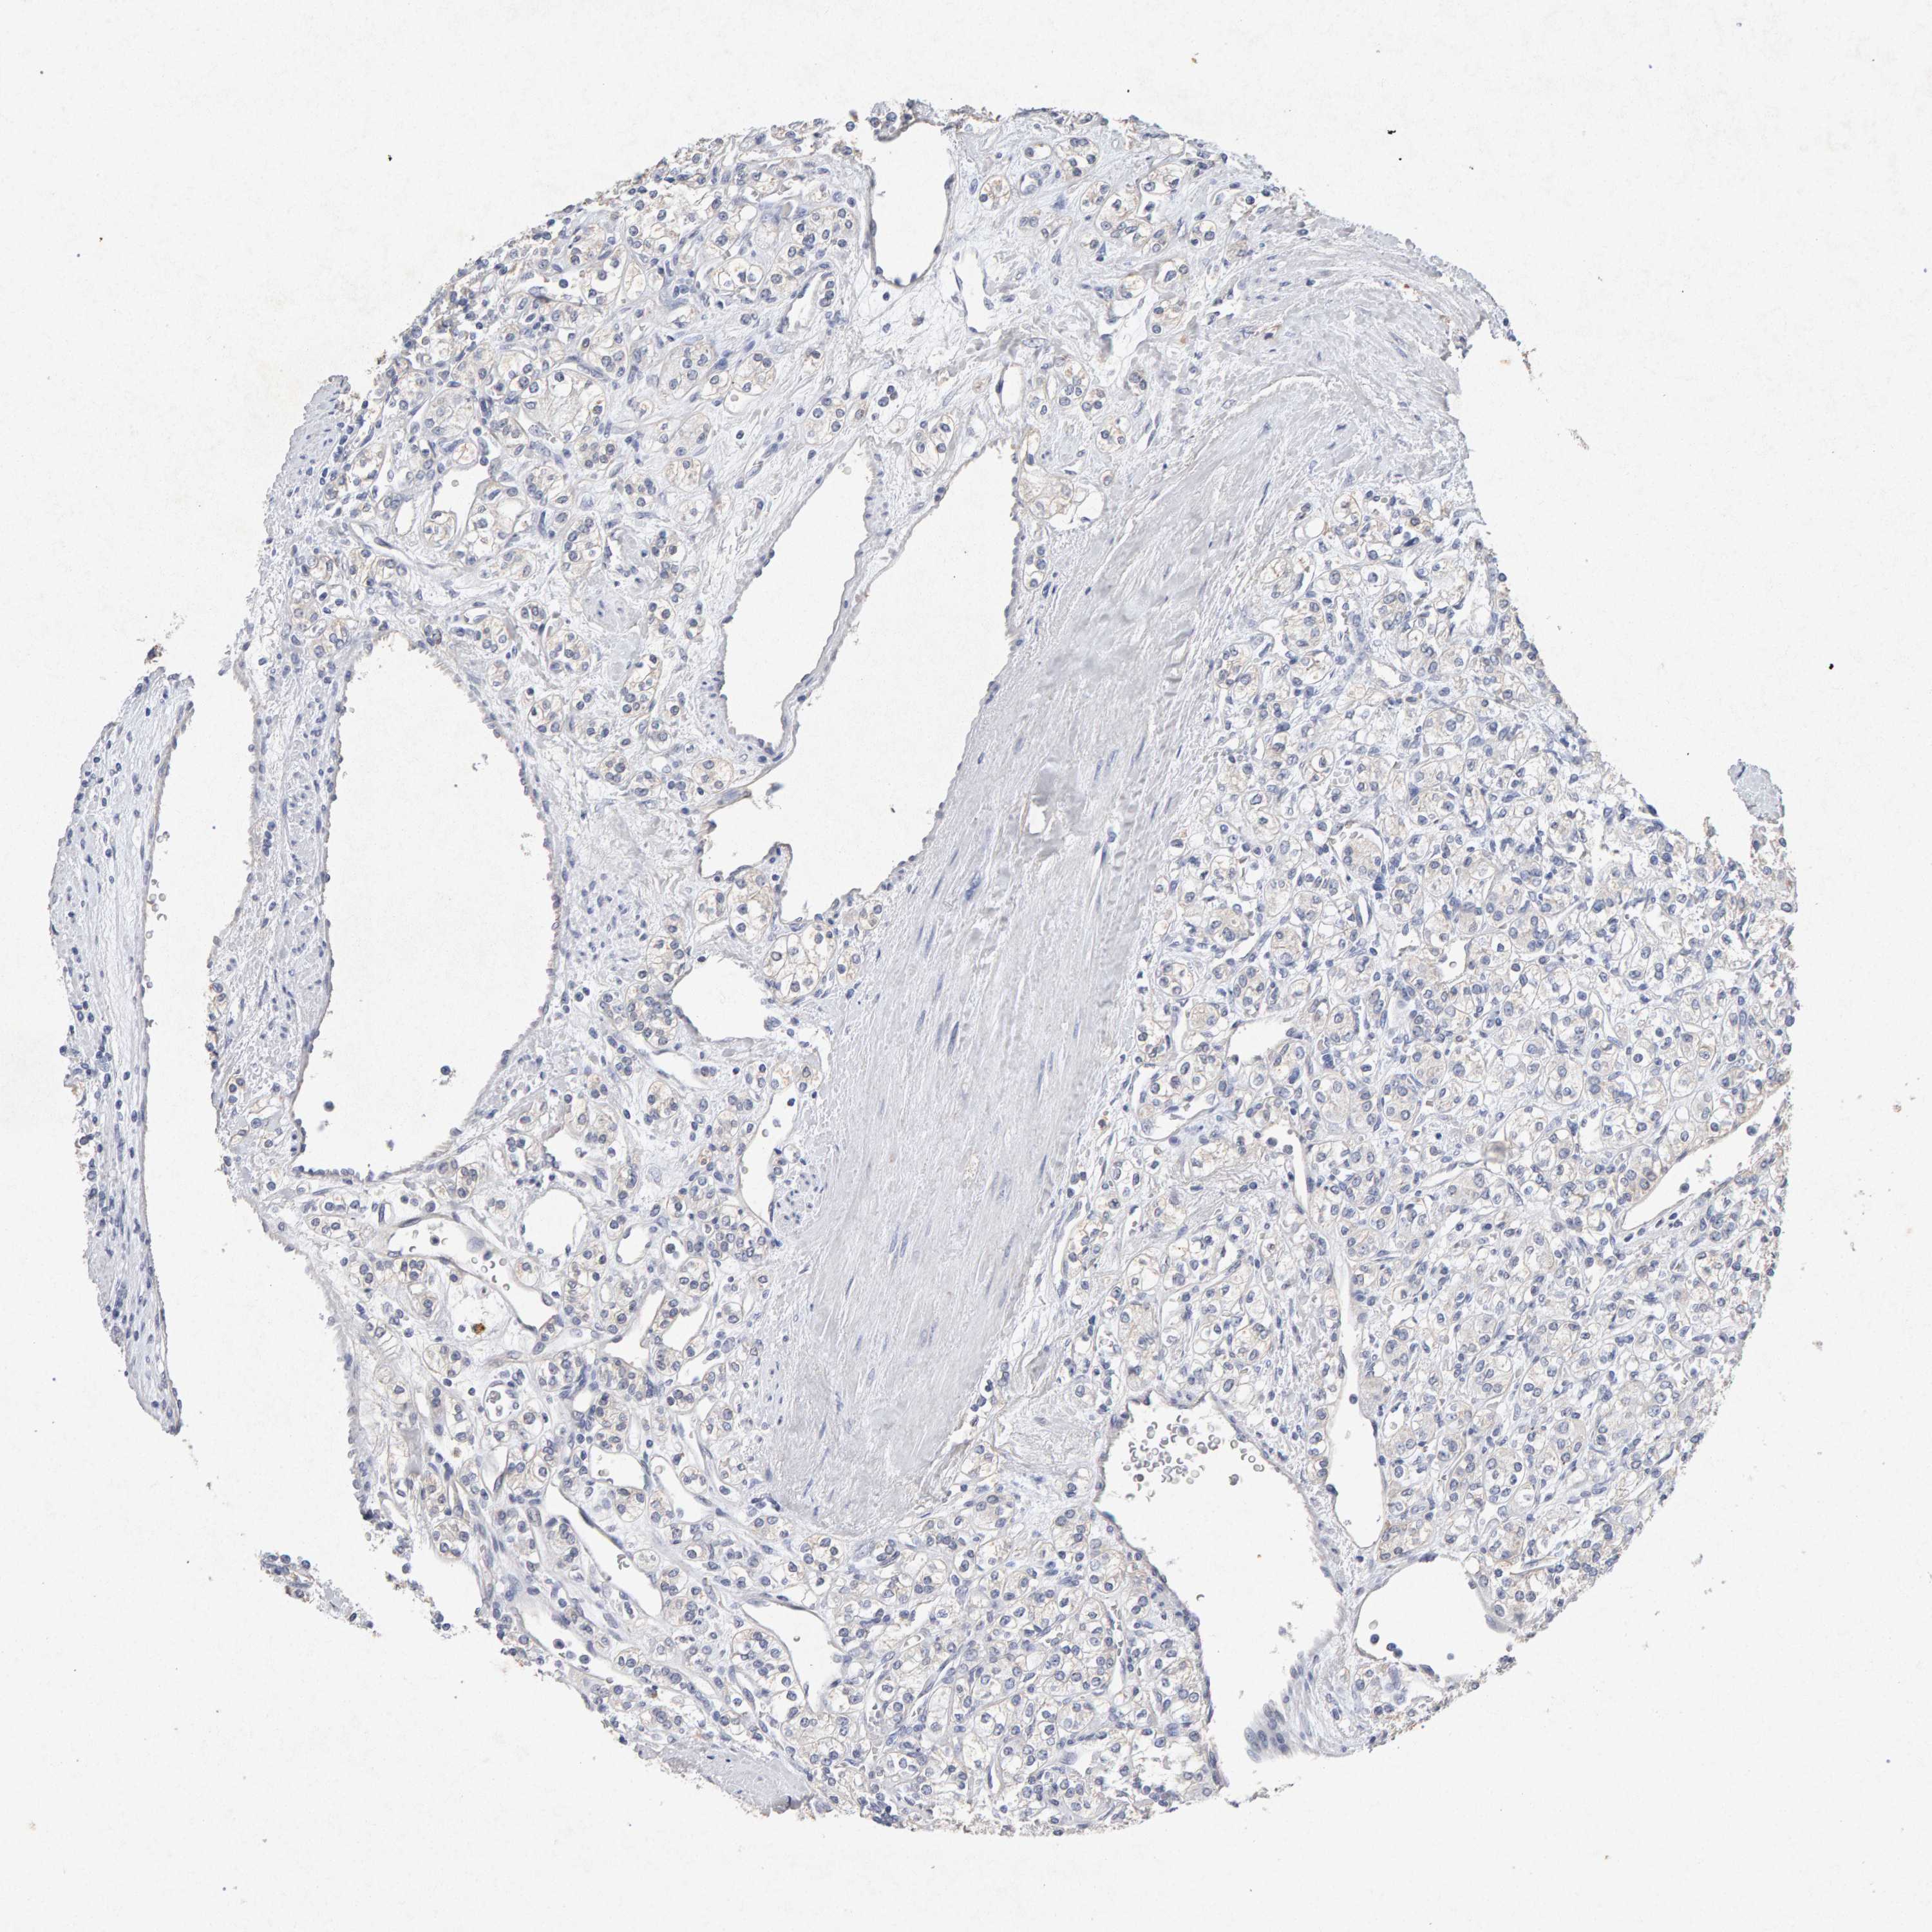

PTPRM is not prognostic in Kidney Renal Papillary Cell Carcinoma (TCGA)

Stage:

Survival analysis